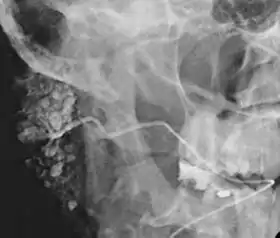

![]() Sialogram in a patient suspected of Sjögren's syndrome | |

This study is interpreted by evaluating the morphology of the salivary ducts for obstructions and chronic inflammation. Sialodochitis is a term describing dilation of the ducts caused by repeated inflammatory or infective processes. There is also irregular salivary duct stricture (narrowing) of the duct, which creates an appearance known as "sausage link" pattern on a sialogram. Suggestions of abscesses and autoimmune diseases such as Sjögren syndrome can also be elicited. Sialadenitis is inflammation of the salivary glands, which may cause acinar atrophy and create an appearance known as "pruning of the tree" on a sialogram, where there are less branches visible from the duct system. A space occupying lesion that occurs within or adjacent to a salivary gland can displace the normal anatomy of the gland. This may create an appearance known as "ball in hand" on an sialogram, where the ducts are curved around the mass of the lesion.[5]